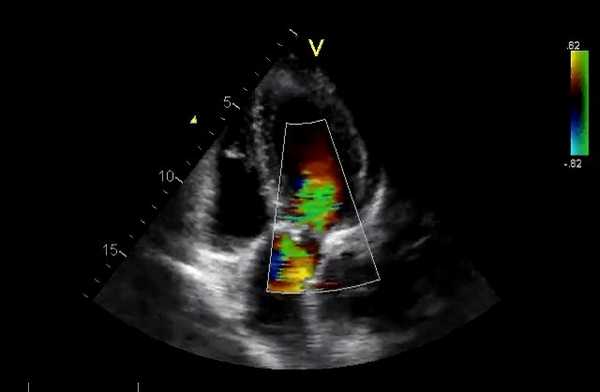

Допплеровская ЭхоКГ очень полезно для оценки функции протезного клапана:

- Препятствие кровотоку. Из-за того, что материал этих клапанов не соответствует требованиям, скорость потока через них отличается от обычных стандартных клапанов (см. Таблицу 6.1). Большинство протезов клапанов создают препятствия для кровотока. Можно произвести ряд измерений:

- Пиковая скорость. Она выше, чем в обычных клапанах, из-за относительно меньшей площади отверстия, обусловленной большим объемом искусственного материала. Пример диапазона приведены в таблице. Как правило, пиковая скорость> 2 м/с в МК обычно указывает на дисфункцию как механических, так и биологических протезных клапанов. Скорость потока в протезе аорты обычно

- Градиент давления (ΔP). Этот показатель рассчитывается по упрощенному уравнению Бернулли (ΔP = 4V2).

- Площадь отверстия клапана - измеряется по уравнению непрерывности

Регургитация. Она может происходить через отверстие клапана (чрезклапанная) или вокруг пришивного кольца (парапротезная). Легкая транскалапанная митральная регургитация может быть обнаружена в нормально функционирующих клапанах, чаще в механических клапанах. Это связано с закрытием клапана или из-за зазоров между разными частями протеза. Ее бывает трудно обнаружить из-за маскировки тенью протеза. Умеренная или тяжелая митральная регургитация всегда считается патологической.

Непрерывно-волновой допплер более полезен, чем импульсный, а цветное допплеровское картирование кровотока (ЦДК) хорошо для отображения антероградных и ретроградных потоков. Турбулентный кровоток регистрируется в виде мозаики цветов. В митральных биопротезах обычно видна одна струя. В большинстве митральных механических клапанов видны 2 струи (почти равного размера у клапанов Старра - Эдвардса, одна меньше другой в клапанах Бьорка - Шайли).

При регургитации может быть несколько струй разного размера в зависимости от типа клапана (например, 2 струи у Бьорка - Шили, несколько у Старра - Эдвардса). ЦДК также помогает различать чресклапанную и парапротезную регургитацию и помогает выявить новую регургитацию.